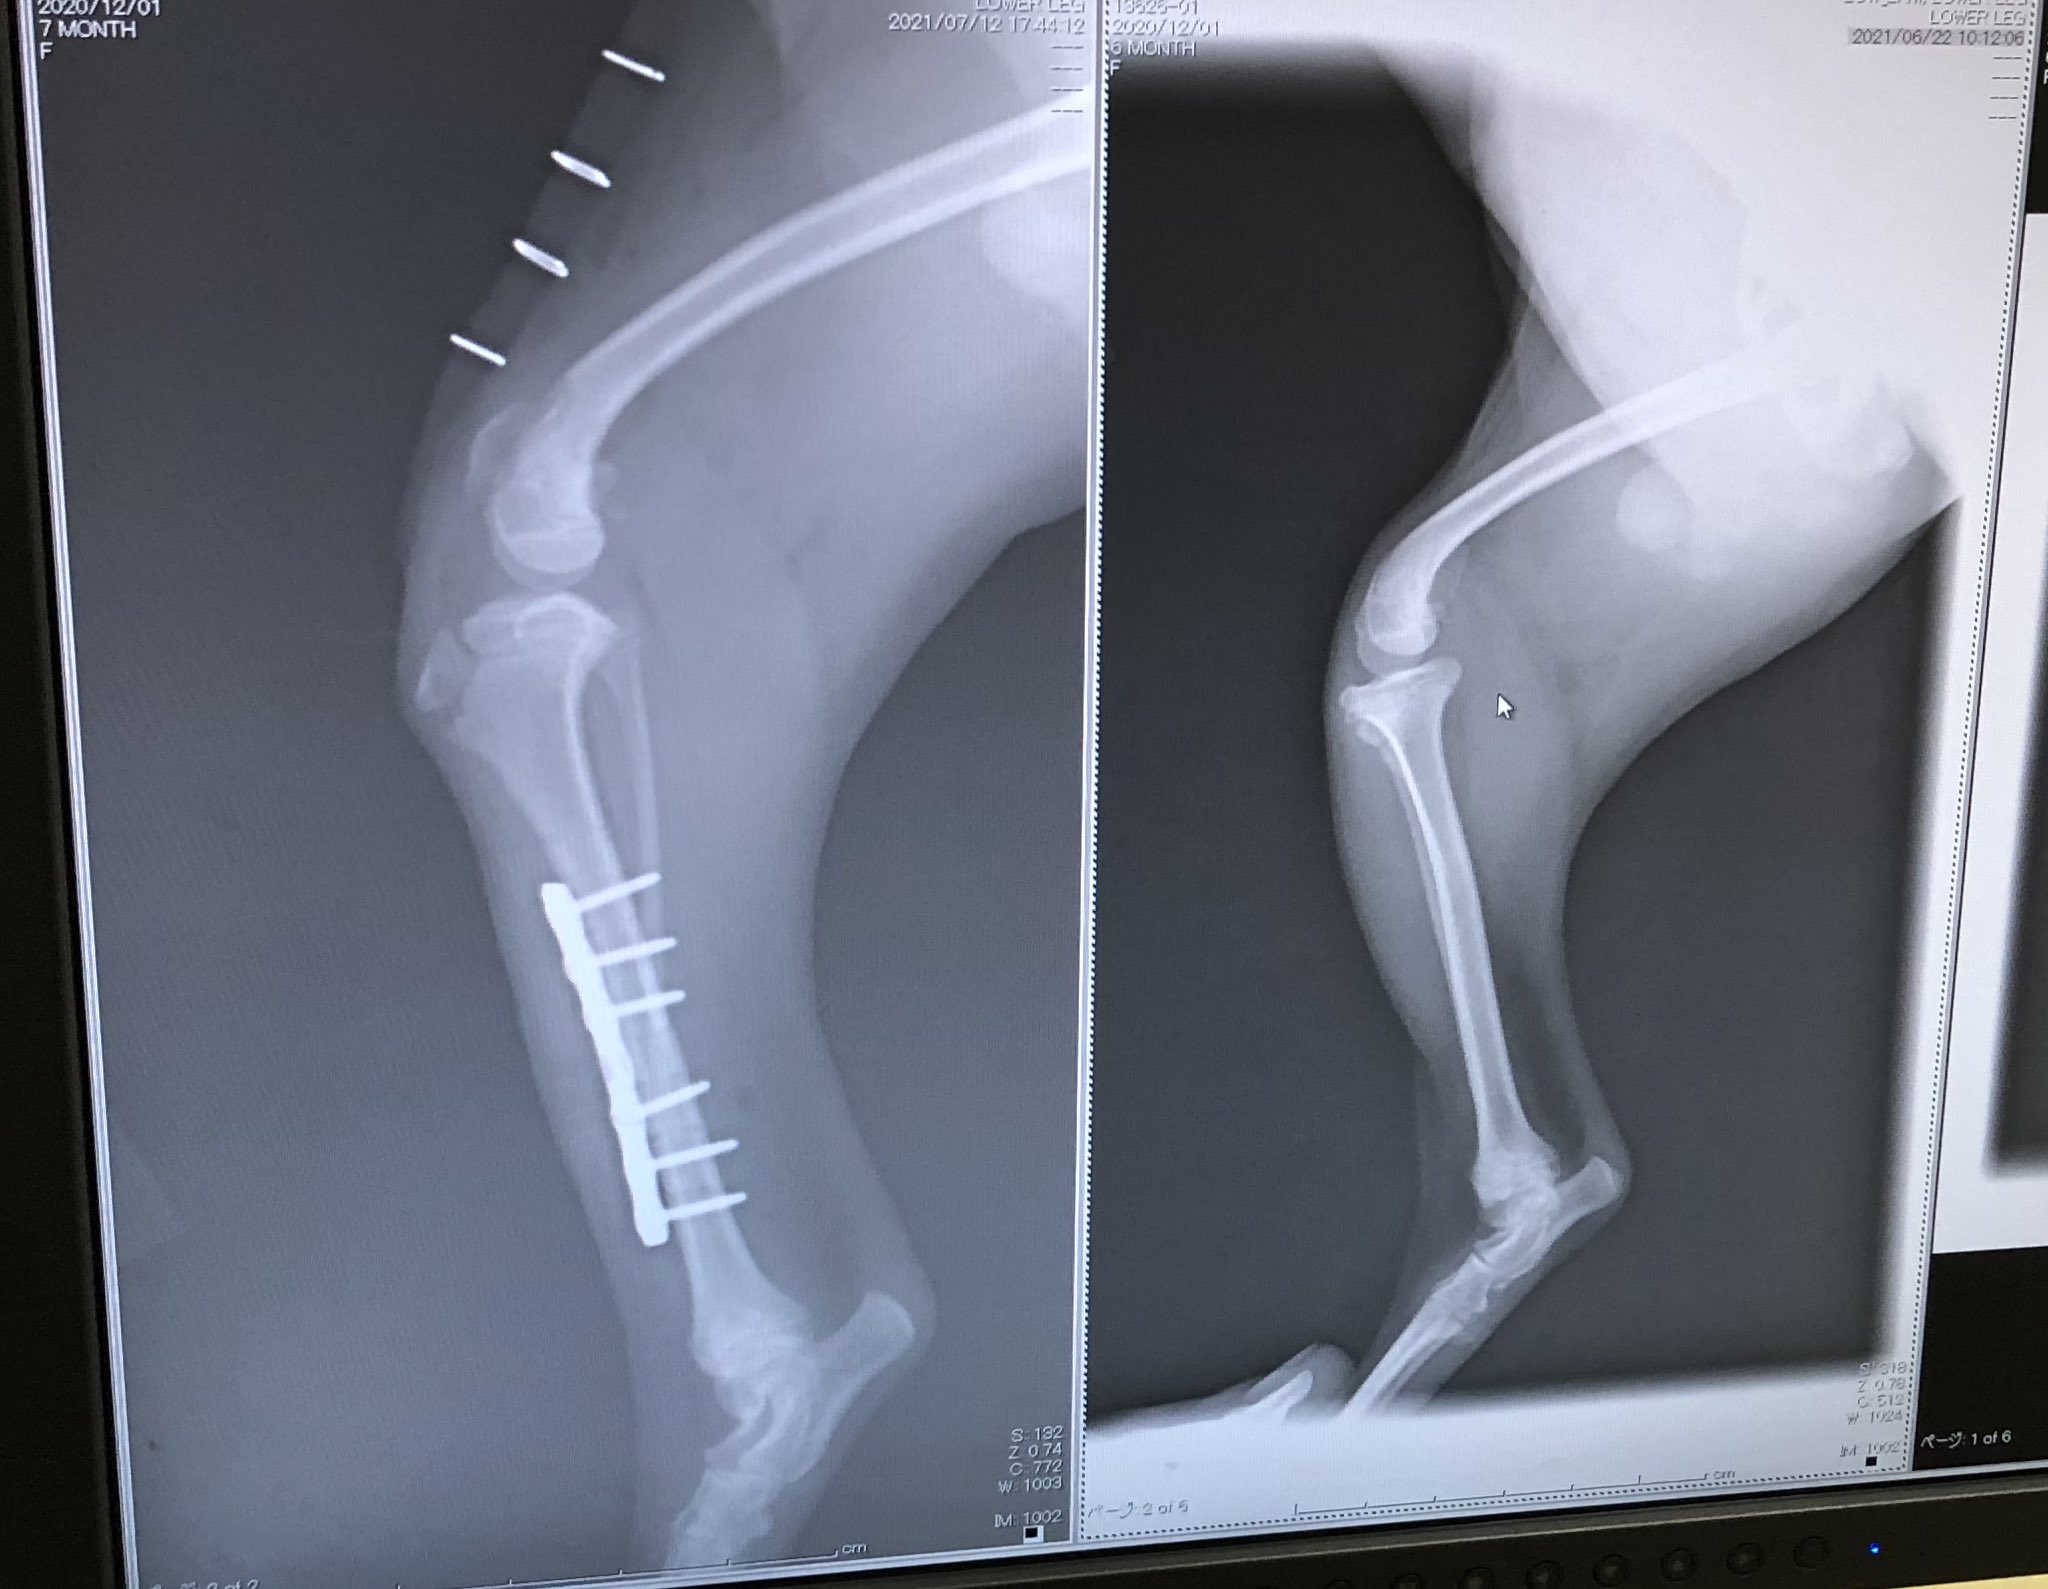

犬の膝蓋骨内方脱臼グレード4による歩行困難 症例:6ヶ月 トイプードル 雌 主訴:3ヶ月前から右後肢を着地しないで上げるようになっており、近医で痛み止めやサプリメントを処方されましたが、最近反対側の左後肢も足を曲げたまま歩けなくなったとの小型犬には良くある事とは聞いていましたが、まさかウチのチワワが急に膝蓋骨脱臼(しつがいこつだっきゅう)パテラと診断されるとは思いもよりませんでした。あの噂の膝(ひざ)のお皿がズレてしまう症状のパテラという膝の病気です。 続きを読む まさか急に膝蓋骨脱臼(しつがいこ膝蓋骨内方脱臼(パテラ) 重症度は4つの分類(グレード)に分けられています。 を適応することによって膝蓋骨脱臼に合併する骨の湾曲を予防することが可能なため小型犬の場合でも手術